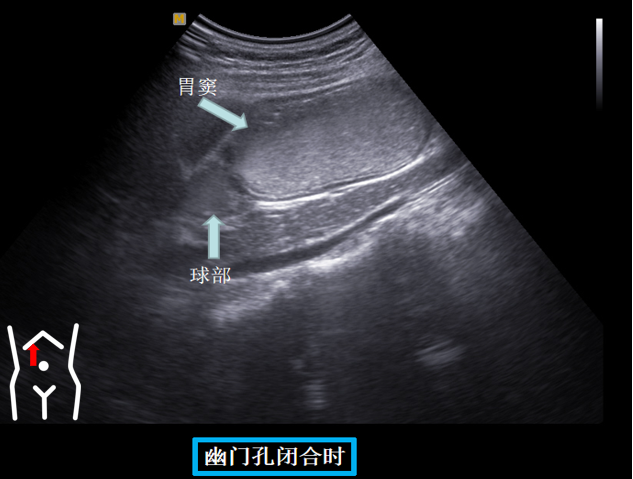

第四组胃窦球部切面

患者从右卧位改成平卧此时头也随着患者改变体位而由横切改为纵切在脐孔与右肋缘连线处扫出胃窦幽门管幽门孔球部降部水平部